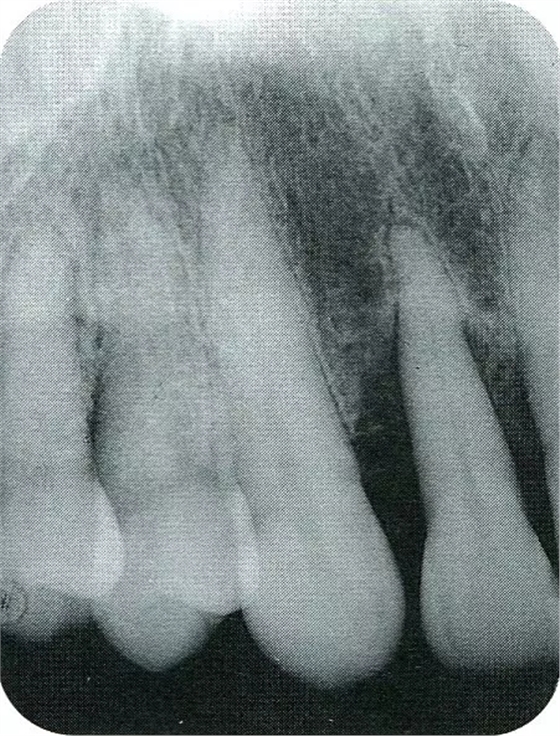

▲圖7-2術(shù)前x片。確認(rèn)存在垂直性深骨缺損。